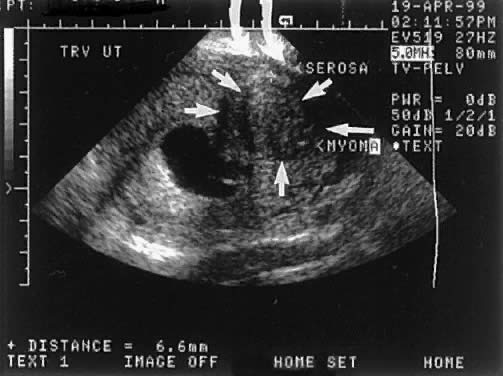

Before the availability of transvaginal ultrasound, hysterography was the most widely used technique for evaluation of the uterine cavity because of the limitations of transabdominal ultrasound. Hysterography allowed for the evaluation of tubal patency.10 The major limitation of hysterography was its poor imaging of the myometrial walls and a significant number of false-positive findings of submucous leiomyomas that were intramural (Fig. 3). Saline contrast hysterosonography using transabdominal ultrasound was initially described by Nanini in 1981.11 Richman and coworkers explored the assessment of fallopian tube patency by abdominal ultrasound after saline injection in 1984.12 Because of suboptimal imaging by the transabdominal technique, hysterography remained the routine approach.

Fig. 3. Example of a T-II intramural leiomyoma. This intramural leiomyoma extends within 2 mm of the serosa and 5 mm of the endometrial mucosa. This type of leiomyoma may be falsely identified as a submucous lesion by fluoroscopic x-ray hysterography.